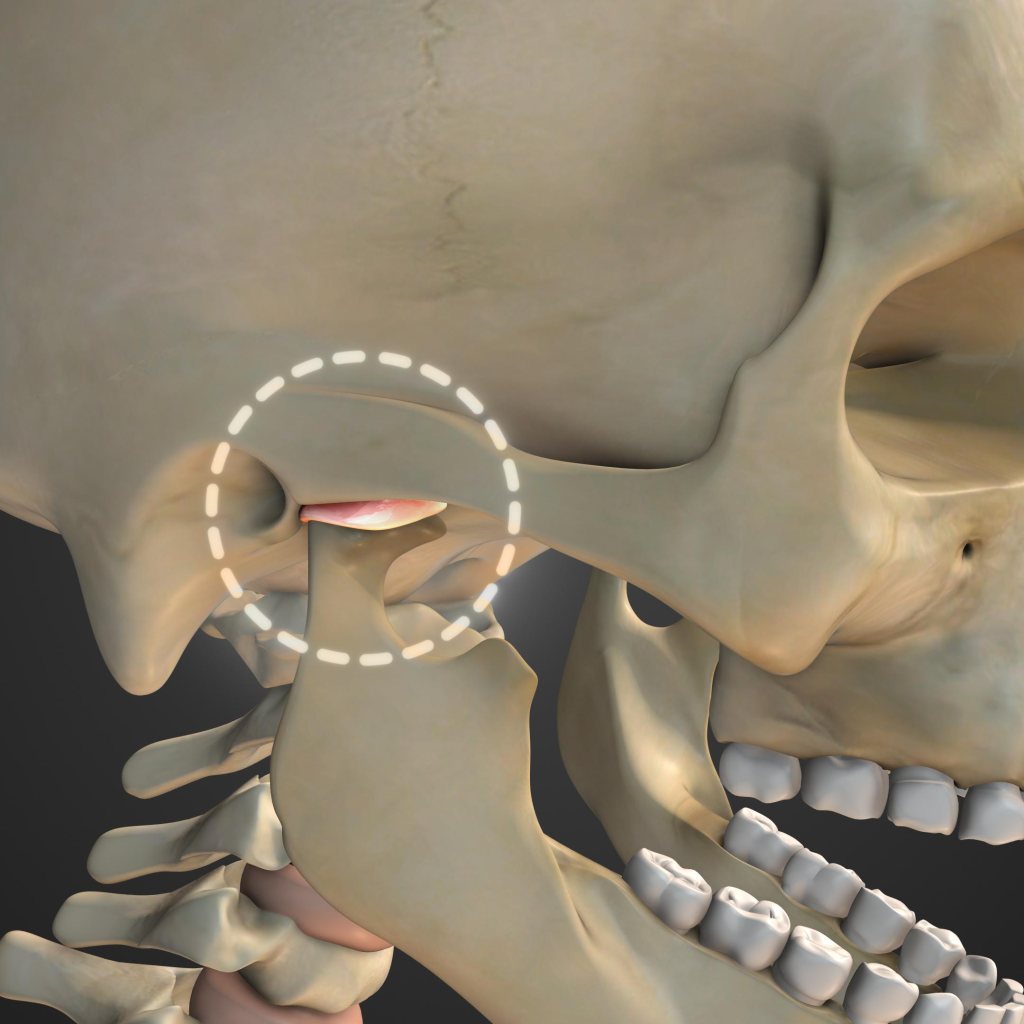

7. Jaw Pain or Difficulty Chewing

Pain while chewing or discomfort in the jaw may be caused by tooth infections, wisdom tooth problems, or TMJ disorders. A dentist can diagnose the problem and recommend treatment.